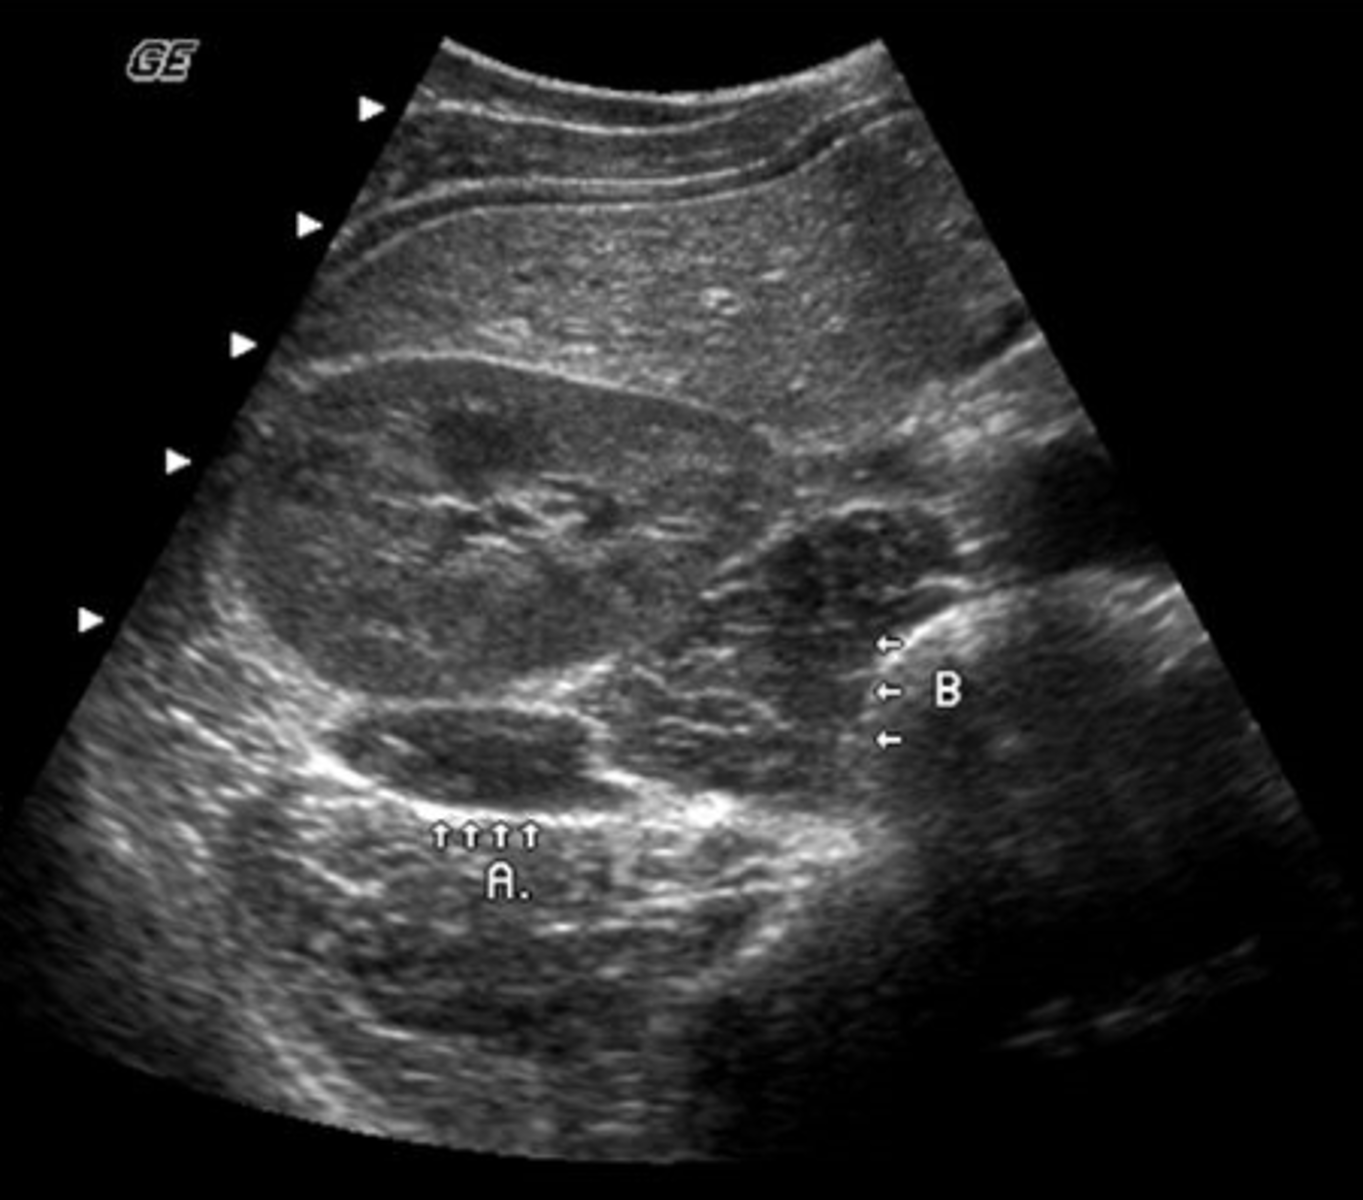

b. splenic and retroperitoneal varices

A 49-year-old male presented with a clinical history of liver cirrhosis and portal hypertension. In the transverse image below, multiple hypoechoic structures are seen at the splenic hilum and between the kidney and spleen. What is the most likely etiology of these structures.

a. multiple aneurysms of the splenic artery

c. loculated ascites

d. polycystic kidney disease

e. fluid-filled loops of bowel